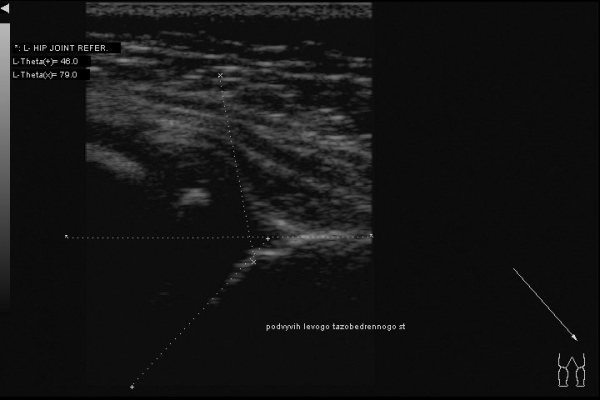

Ребенок 6 месяцев, до обращения в наш центр неоднократно осмотрен ортопедами. Клинически -- полная норма, но насторожила какая-то чуть избыточная ротация в левом бедре. Решил выполнить УЗИ:

По УЗИ дисплазия слева, достаточно тяжелая. Может и подвывих, если придраться.

А на рентгене -- полный врожденный вывих, головка лежит вне сустава.

Тактика лечения -- другая, прогнозы - другие.